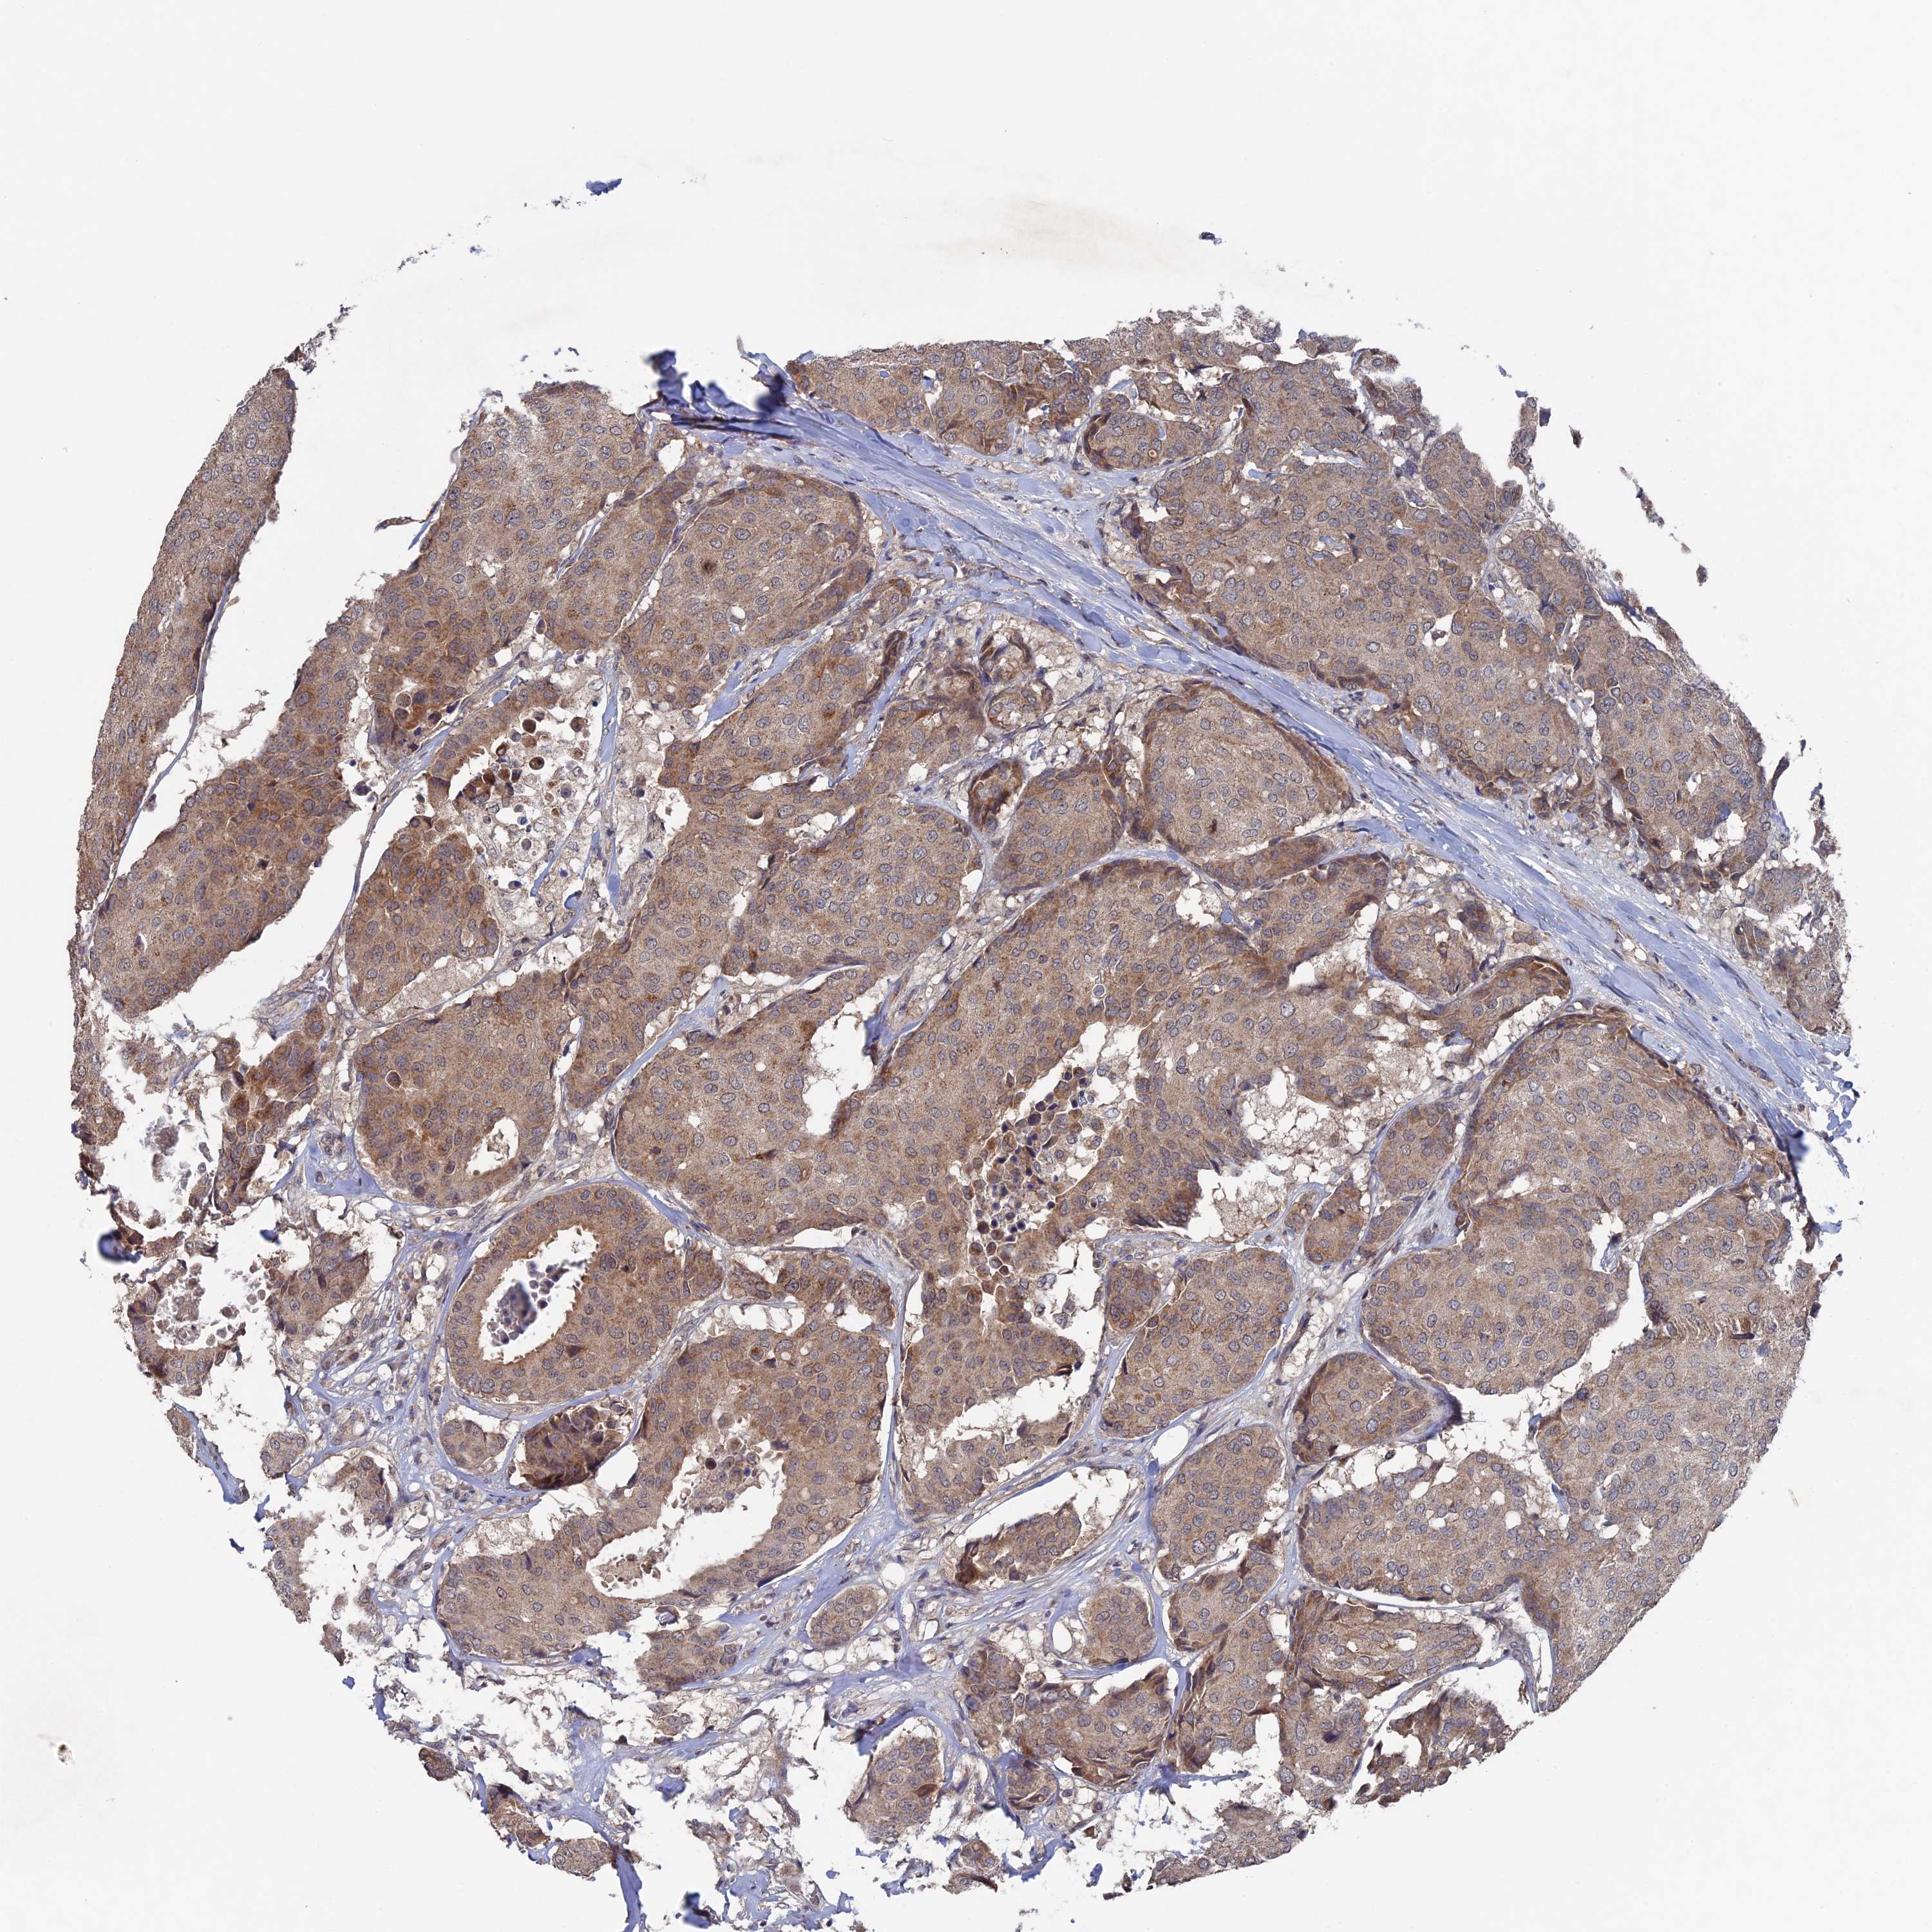

BRCA TCGA BRCA VALIDATION PROTEIN EXPRESSION